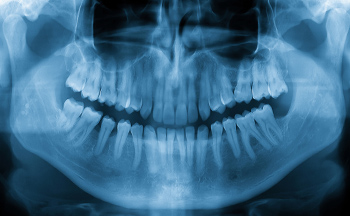

精密検査によるオーダーメイドの 噛み合わせ分析を実施

「入れ歯を作ったけれど痛くて使えない」ということがないように、当院では目に見えない骨の状態をパノラマレントゲンや歯科用CTで診断し、レイフェイスやフェイスボウトランスファーを用いて、患者さま固有の噛み合わせの位置をミリ単位で計測しています。充実した先端設備による多角的な分析により、長時間の食事でも疲れにくく、痛みやガタつきのない精度の高い入れ歯のご提供を目指します。

パノラマレントゲン

お口の中全体を1枚のレントゲン画像に映し出す検査装置です。歯並びの全体の状態を確認でき、精密な治療計画の立案に役立ちます。